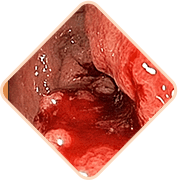

- Vratite tonus i elastičnost vena zahvaljujući ekstraktu stolisnika, ekstraktu palmetto pile

- Započnite regeneraciju tkiva anusa zahvaljujući ekstraktu palme sabal, kore hrasta, aloe

- Uklonite infekcije i gnojne procese zahvaljujući kamilici, krumpiru i poštenju

- Sprječava povratak hemoroida zahvaljujući celandinu